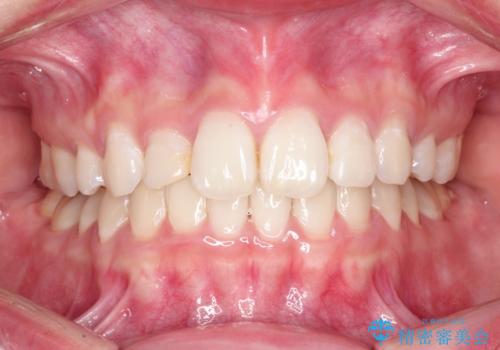

ハーフリンガル矯正 抜歯をして前歯を下げる

- ハーフリンガル

- 1年8ヶ月

上顎の抜歯により上の前歯の位置を大幅に後ろに下げることができます。

奥歯の位置関係など、様々な要素を加味し、適応を判断する必要があります。